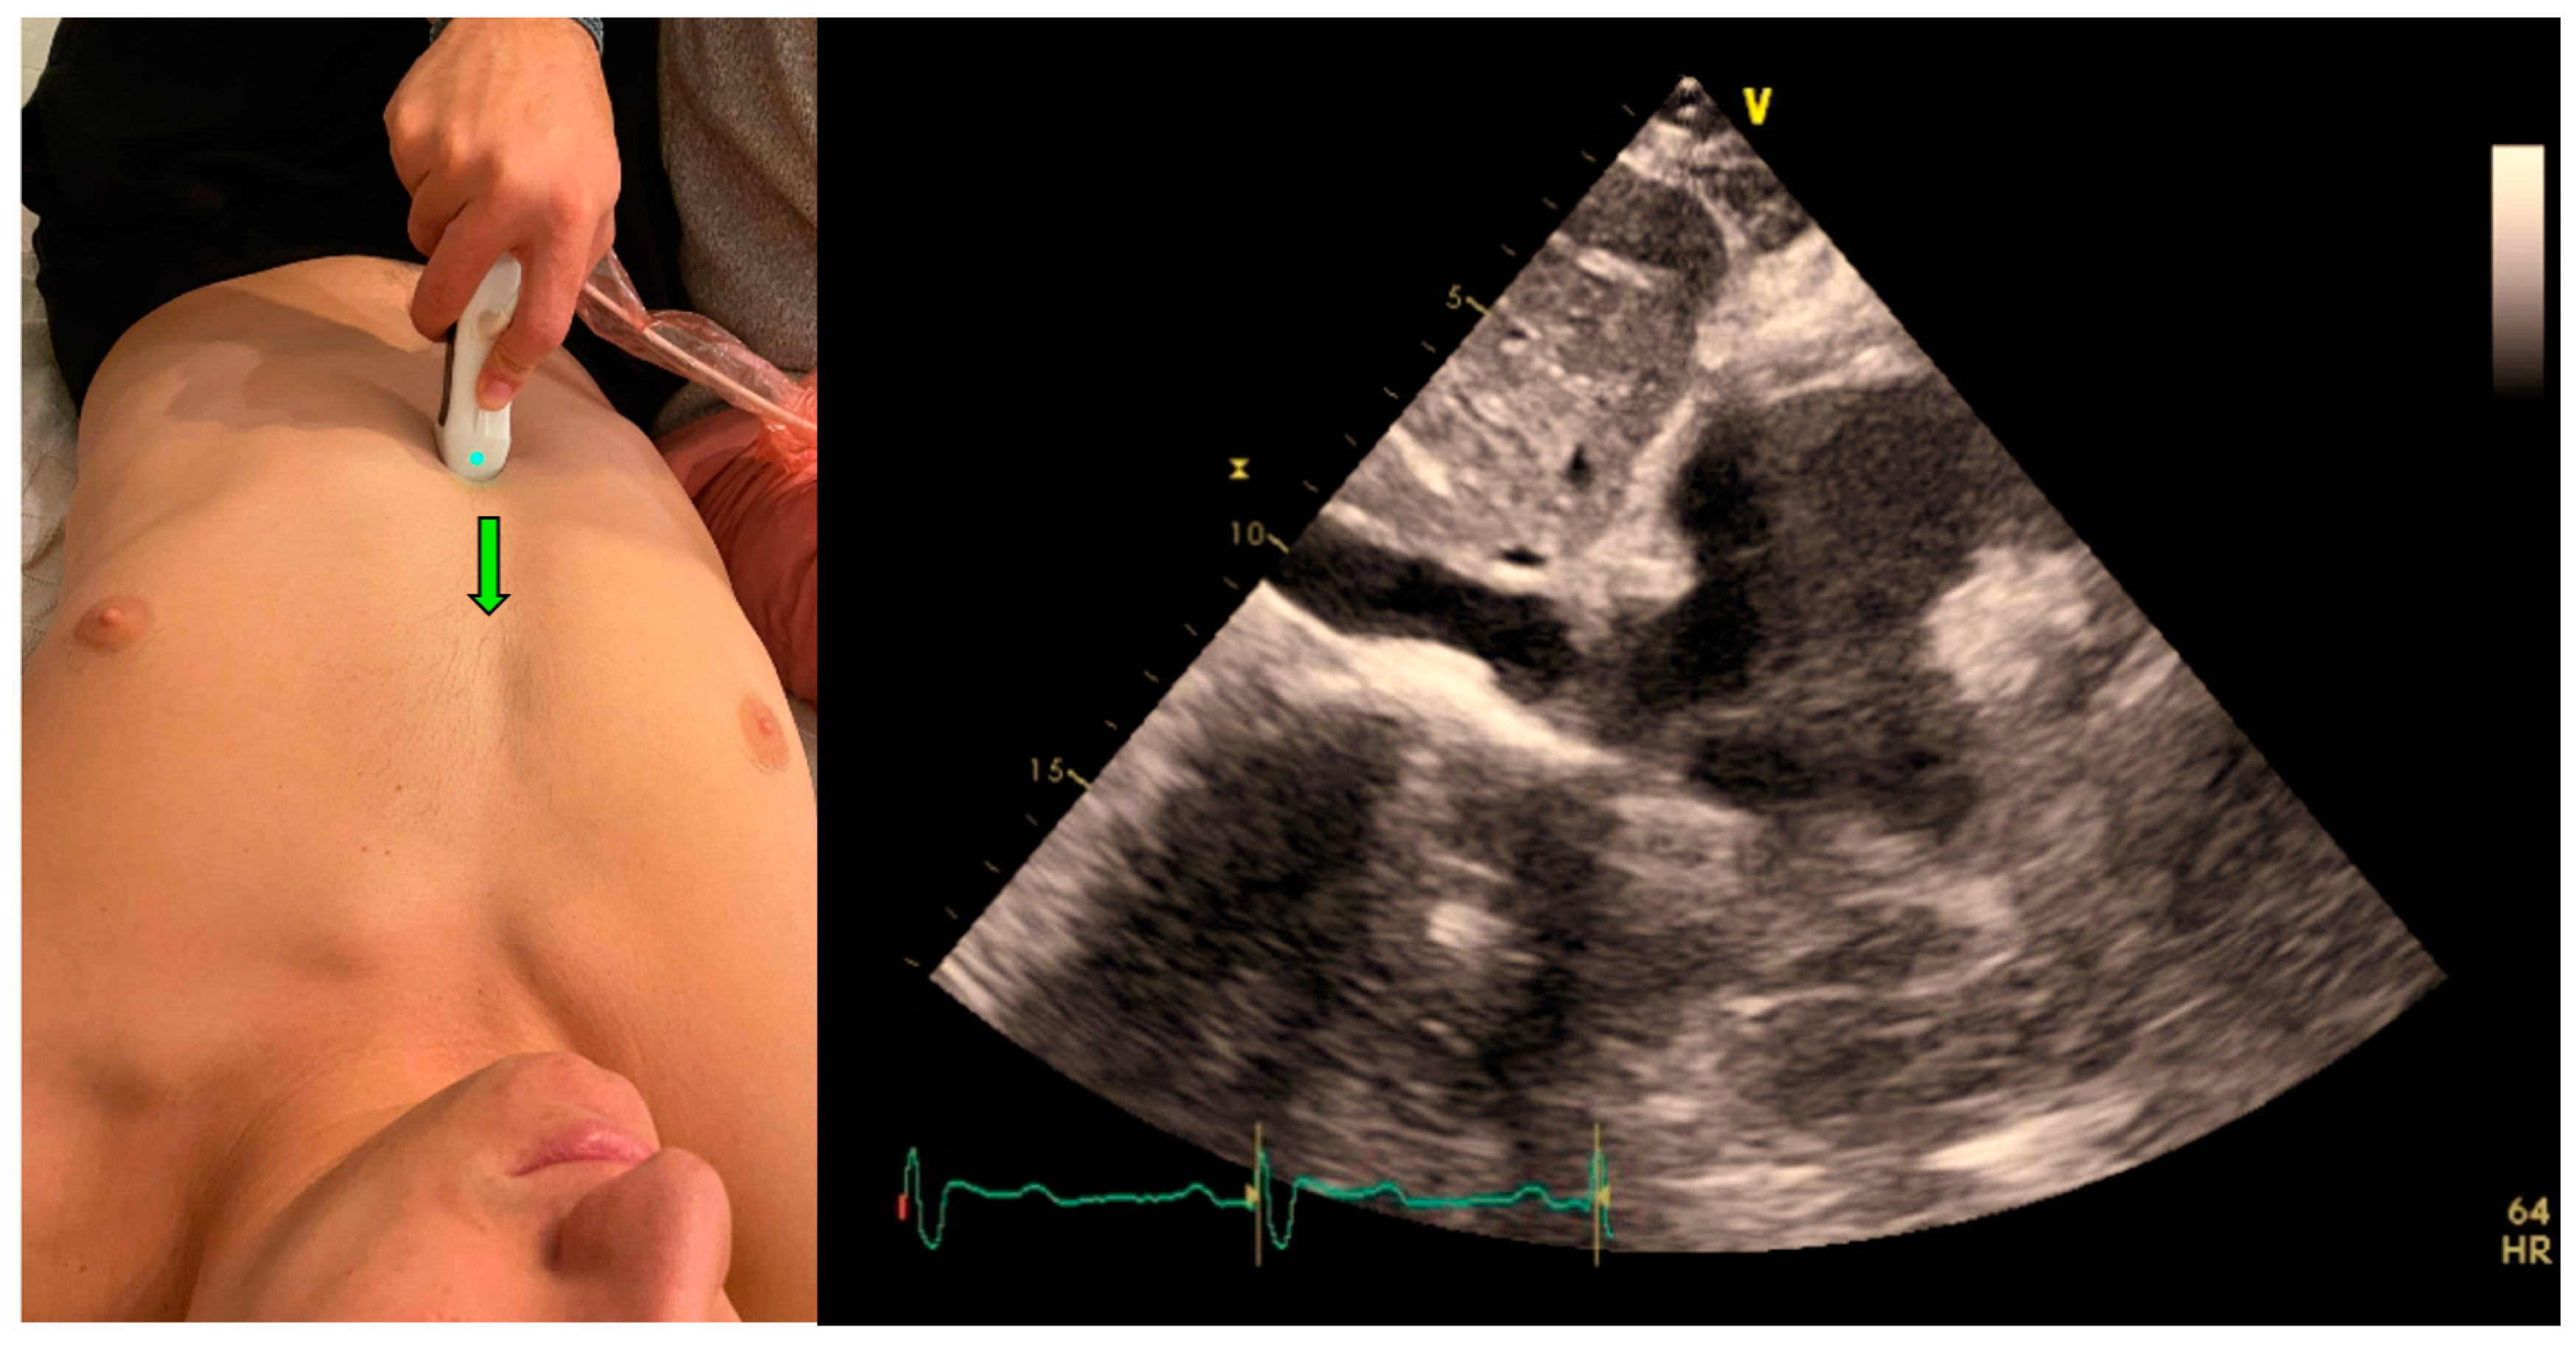

4. The IVC Collapsibility Measurement

The IVC clips were taken from the subcostal IVC view (Figure 3). In this view, the maximum and minimum diameters of the IVC throughout a respiratory cycle were measured two cm from the IVC-right atrium junction, using M-mode, providing the CI that represents the collapsibility of the IVC.

Figure 3.

Acquisition (probe point—green arrow) and anatomy of IVC View.

Following imaging acquisition, a post hoc analysis of the acquired IVC clip was performed in two different manners: (1) Using a real-time, machine-integrated, automatic IVC tool, and (2) by the expert physician, blinded to the automatic assessment, who examined the same clip frame-by-frame and measured the CI manually. The CI is presented as a percentage of the IVC collapsibility (minimal IVC size divided by the maximal IVC size).